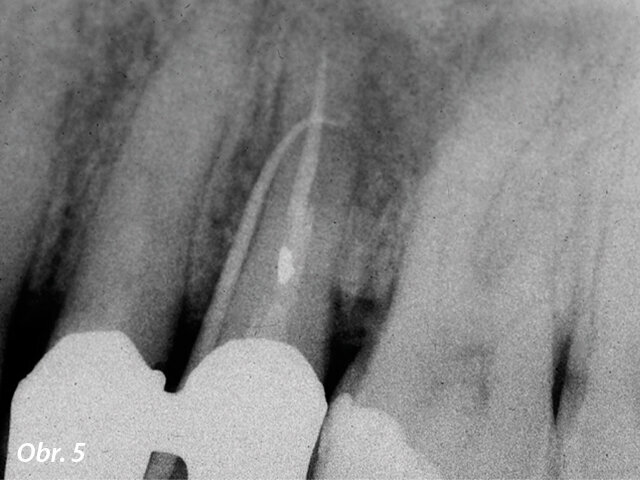

U horního premoláru na obr. 5, 6 odhalil fistulogram přítomnost apikální léze, která zasahovala koronálním směrem asi do střední třetiny kořene. Rozhodování o klinickém postupu tedy mohlo vést k ortográdní revizi endodontického ošetření. CBCT nám ale poskytlo zcela jiný pohled na situaci v porovnání s intraorálním snímkem, ukázalo totiž, že byl zub při předchozím ošetření nevratně poškozen a musí být extrahován.